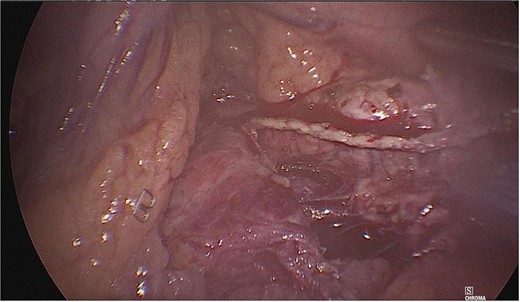

Dissection of the pancreas (body and tail) and splenic vascular structures (arteries and veins; Fig. 5). Intrapancreatic veins were identified. Dissection was performed with a harmonic scalpel of the pancreatic tissue of the vein, taking care not to disrupt it, and the dissection of vascular structures was completed, thus obtaining splenic preservation. The piece was removed, fibrin sealant was applied to the surgical site (Tisseel), and a drain was placed (Fig. 6). The patient had a satisfactory postoperative course and was discharged with a drain in place to be followed up in the outpatient clinic.

Dissection of the pancreas (body and tail) from splenic vascular structures (artery and vein).

Extraction of the anatomical piece preserving vascular structures.